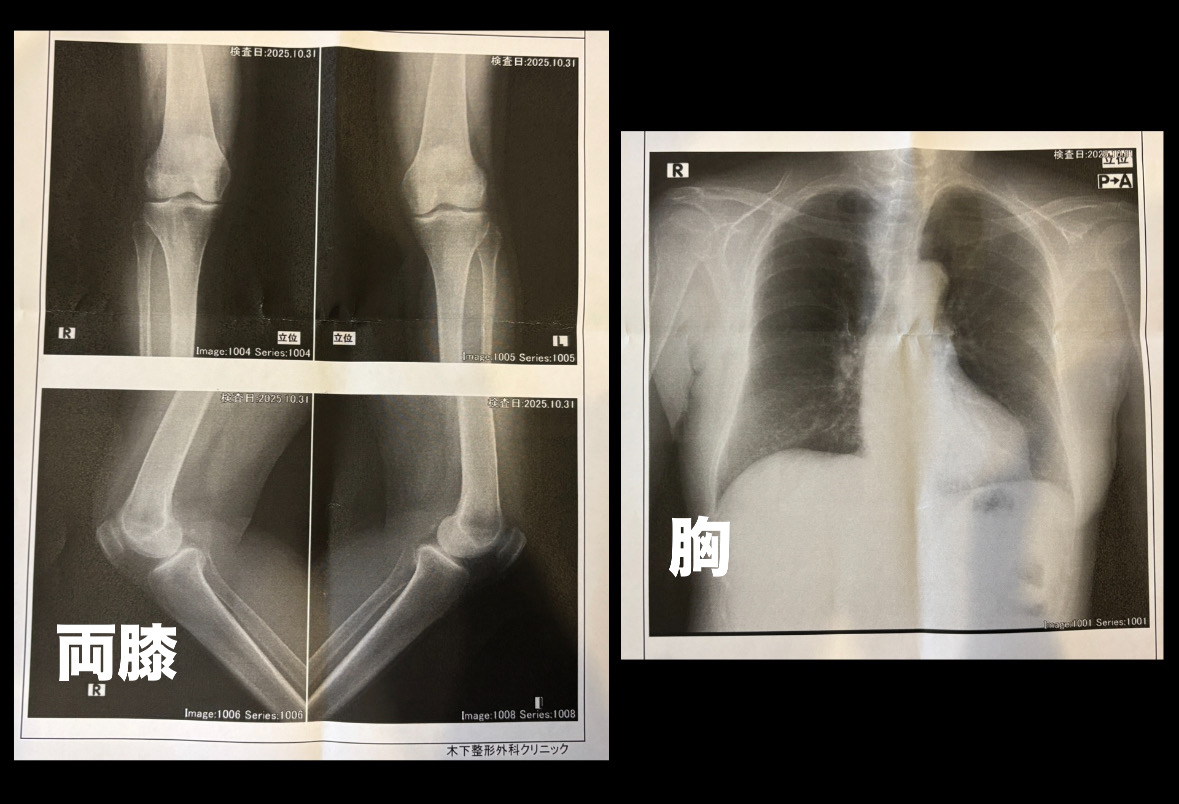

気持ちに余裕がでてきた10月28日火曜日、不注意にも自宅お風呂場で転倒、両膝を強打、胸も打ってしまいました。激痛でしたが、歩行が出来ましたので、骨折はしてないと思い病院に行きませんでした。時間が経つにつれ、痛みと腫れがでてきましたので、昨日、足と胸のレントゲンを撮っていただきました。結果は、骨折もなく打ち身だけでした。